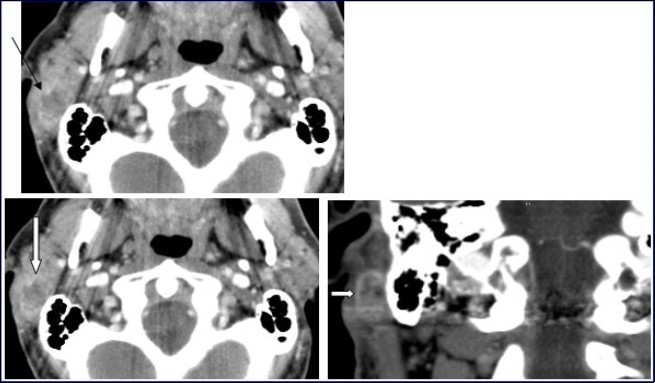

A 54-year-old man consulted for right retro-auricular mass, painless but pruritic, lasting for two months and growing fast. No significant findings in the medical or surgical history. Physical examination revealed a right retro-auricular mass, fixed to the underlying soft tissues measuring 4 x 3 x 3 cm3. The mass had a fluctuating center and there were signs of inflammation around it. Head and neck examination didn’t show any abnormalities or lymphadenopathy. Oto-Rhino-Lyryngologycal and whole-body examinations were unremarkable. Laboratory studies resulted within normal limits. A short course of antibiotic therapy was initially given without any results. Fine needle aspiration (FNA) cytology revealed parotid malignant tumor without precision. The chest-X ray was normal. Head and neck CT with intravenous contrast material showed a focal lesion in the right parotid gland with size 3 × 2 cm2, well-defined, heterogeneous with peripheral contrast enhancement and necrotic center. No evidence of pathologic lymph nodes in or around parotid gland or bony involvement (Figure 1) was found.

Figure 1.Computed Tomography of the neck with intravenous contrast material revealed a focal lesion in the right parotid gland with size 3 × 2-cm. The mass was well defined, heterogeneous, with peripheral contrast enhancement (large white arrow). It had a central attenuation value of 13 HU, suggesting a necrotic mass without bony involvement (thin black arrow).